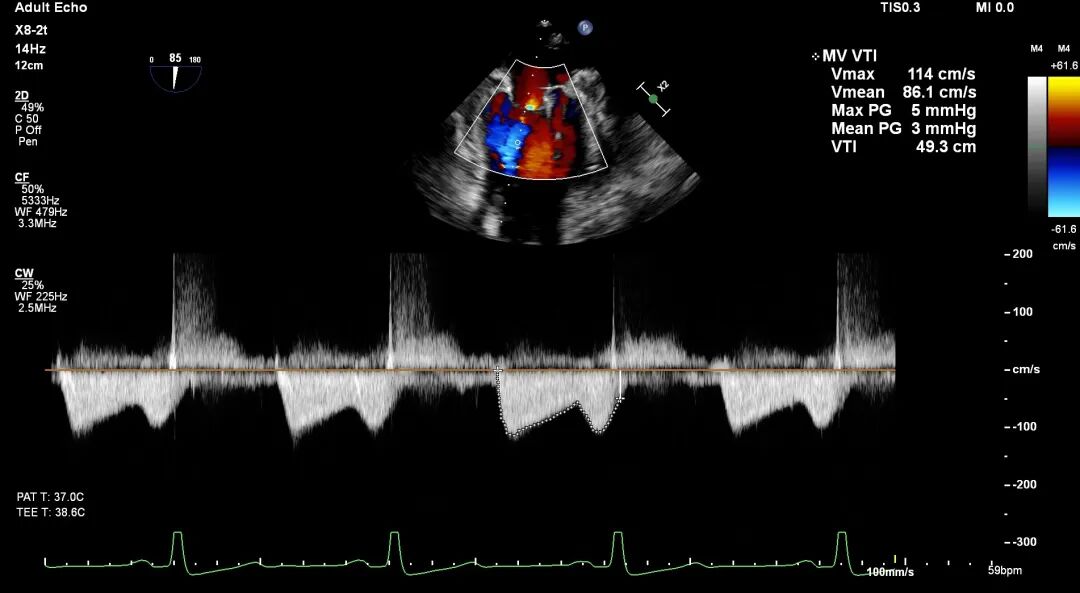

术前TEE评估

原发性MR,交界C1区脱垂,反流程度4+;二尖瓣瓣口面积3.88cm²,平均跨瓣压差2mmHg;二尖瓣前叶(A1)长度16.2mm,二尖瓣后叶长度(P1)长度9.9mm,脱垂高度6mm。